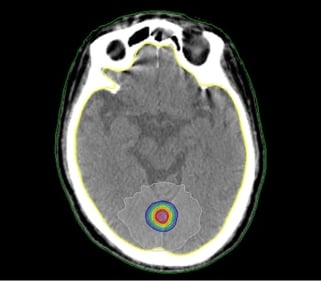

SRT(定位放射線治療)

ターゲットに対して放射線をピンポイントで照射することにより、線量を集中させて治療を行う方法です。一度に高線量の放射線をがんの部分に照射することができるため、治療は数回で終了します。これにより、正常組織への影響を低減しながら、がんの部分をしっかり治療することが可能になりました。放射線をピンポイントで照射するために、治療部位の位置合わせをより精密に行う必要があります。治療中は体全体を極力動かないように固定するなどの対策を講じることで、より正確な照射が可能となります。